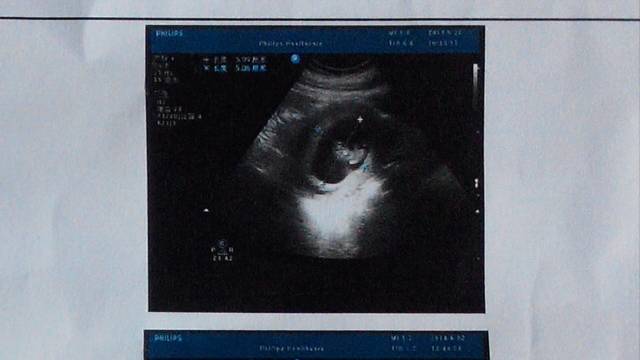

看看我的宝宝健康吗?发育的好不好 看看我的宝宝健康吗?发育的好不好 点击展开 馨逸麻麻 2014-06-27 19:52 为您推荐: 其他回答 要看字才知道 ╭蛊毒〃 2014-06-27 20:12 这几个月啊? 可爱小妈咪 2014-06-27 20:09 相关问题 谁来帮我看看我宝宝发育正常不? 我怀孕32周了请帮我看看我的宝宝发育正常吗? 请医生帮我看看宝宝发育得好不好,怀孕13周+3天,谢谢!